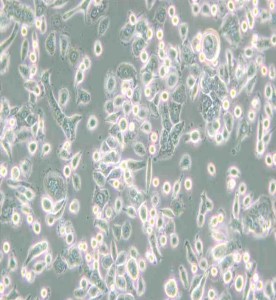

AsPC-1人轉移胰腺腺癌細胞主圖

AsPC-1人轉移胰腺腺癌細胞

Catalogue No :  C199

Product Format :  a T25 flask

Culture Properties :貼壁

Complete Growth Medium :  89%1640+10%FBS+1%雙抗

Atmosphere :  air, 95%; carbon dioxide (CO2), 5%

Application :  Cells and cancer research